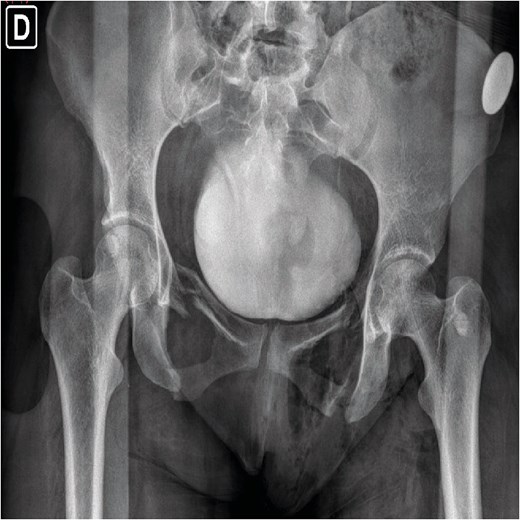

A 30-year-old female patient was admitted to the emergency department after falling from a truck and subsequently being run over by the same vehicle. Initial assessment revealed polytrauma with an unstable pelvic ring fracture and vaginal laceration, characterizing an open fracture. Imaging studies, including X-rays (Fig. 1) and computed tomography (Fig. 2), confirmed a Tile C3 fracture with bilateral vertical instability, classified as a lateral compression type III according to Young-Burgess [3]. Additional findings included a sacral fracture in Denis zone 2 on the right, disruption of the left sacroiliac joint, a mild right-sided pneumothorax, and a mild abdominal contusion. The vaginal laceration, ⁓5 cm in length, was successfully sutured by the gynecology team in the emergency room, with no immediate signs infection. The Injury Severity Score (ISS) was estimated at 33, reflecting the severity of the polytrauma (Table 1). Although hemodynamically stable, the patient was to the intensive care unit (ICU) for hemodynamic monitoring due to the risk of instability.